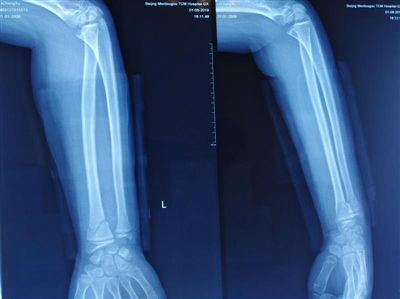

整复前

经X线片检查提示左桡尺骨双骨折。接诊医生向患者家属交代病情后,家属害怕全身麻醉会给患儿带来健康隐患,还涉及二次手术、留下疤痕、切口感染……坚决要求保守治疗。接诊医生考虑该患者为11岁,骨骼生长塑性能力很强,骨折断端在同一水平面上,骨折位置靠近腕关节,骨折断端向掌侧成角畸形,接诊医生采用闭合手法。为使外固定的力量变得富有弹性,选用柳木材质小夹板予以外固定。

闭合整复小夹板外固定后,即刻复查X线片见桡尺骨骨折对位对线优良,指导患者握拳活动。